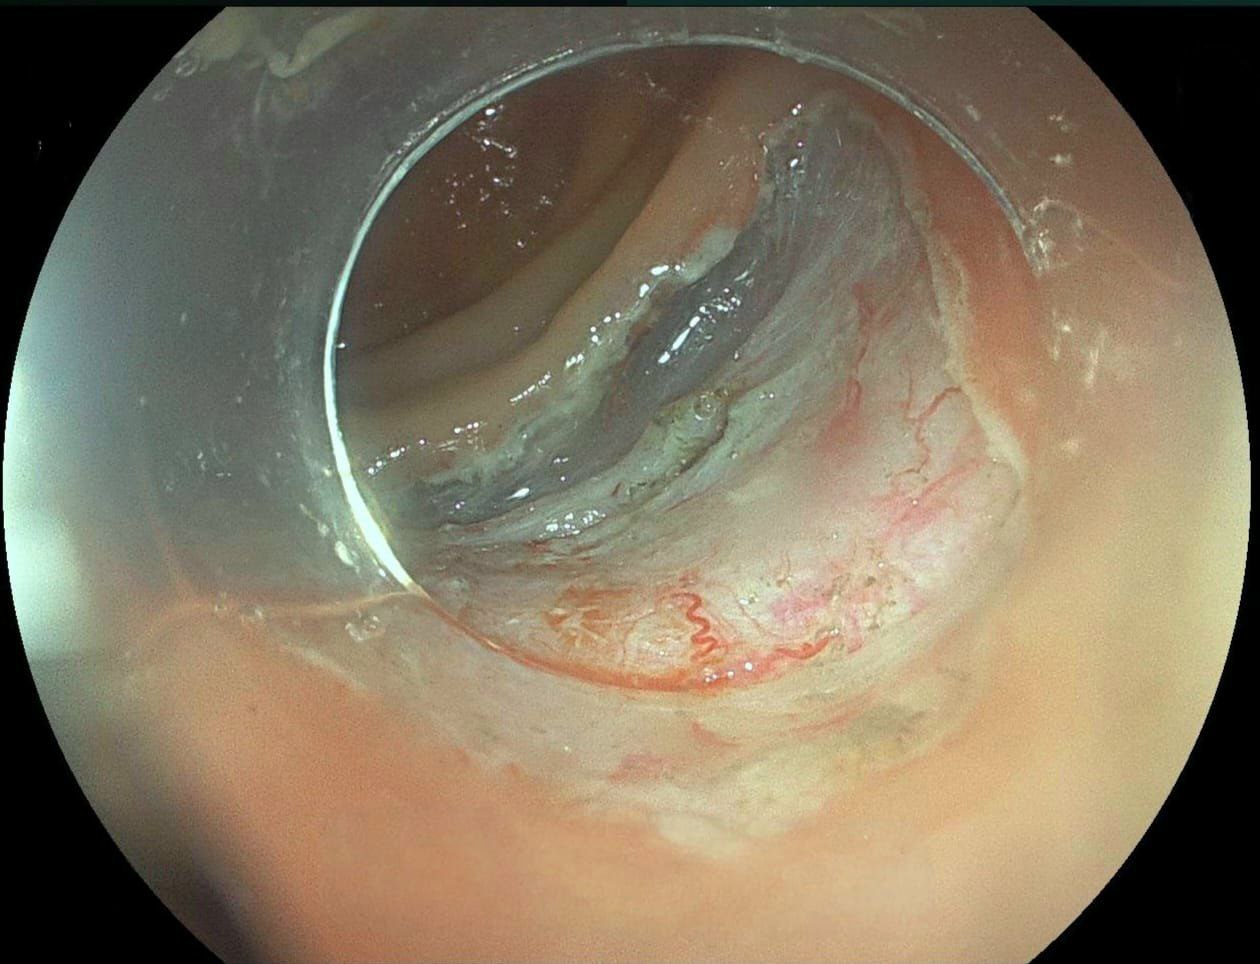

В Амурском областном онкологическом диспансере впервые внедрили методику по удалению новообразований толстой кишки без разреза брюшной полости. Специалисты провели эндоскопическую диссекцию 66-летнему мужчине с раком толстой кишки в 1,5 сантиметра. Эта методика позволяет избавлять пациента от злокачественных образований в слизистой оболочке на самых ранних стадиях с минимальным риском осложнений.

"Ранее крупные образования мы удаляли лапораскопическим методом (через небольшие надрезы), что несет небольшие риски осложнений. Внедренная эндоскопическая подслизистая диссекция помогает полностью удалить образование в пределах здоровых тканей, избегая травматичного вмешательства. Операция выполняется эндоскопическим способом", - прокомментировали в Амурском областном онкологическом диспансере.

Фото Минздрава Амурской области